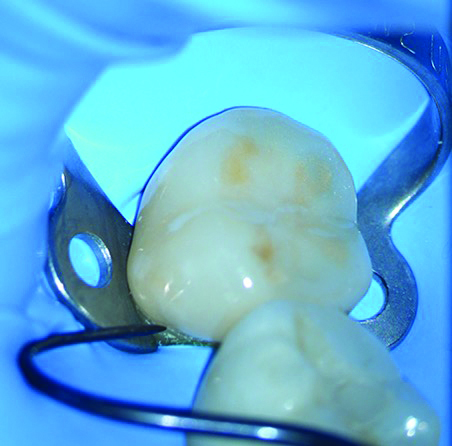

The final step of the clinical workflow involves complete isolation of the operative site using a rubber dam under the DOM to prevent contamination before cementation. After isolation was achieved the restoration was tried in to verify full seating, thus ensuring a precise marginal fit and tight proximal contacts, with smooth transitions and no overhangs (Figure 16).

Fig 16. Initial intraoral fit check, from all aspects, was done under the microscope, directly and indirectly.

Figure 16